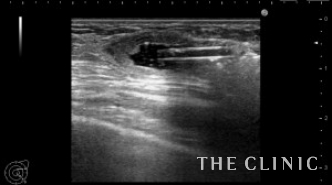

他院でヒアルロン酸豊胸を行った方ですが、炎症のためヒアルロン酸の周囲に非常に厚い被膜が形成され、瘢痕化していました。

しこりは両側の乳房全体にあり、一部は以前ヒアルロニダーゼで吸引しました。

被膜は肥厚して中心にわずかにヒアルロン酸があります。

ヒアルロニダーゼで溶解して吸引しましたが、被膜は残存しています。

エコーとの比較です。

このしこりは内腔がありヒアルロン酸がありました。

ヒアルロン酸注入によるしこりのエコー診断カルテ